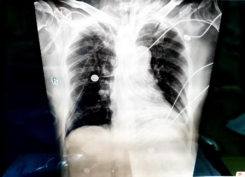

急诊胸部正位片: 1.双肺透过度减低,纹理模糊,散在索条,请结合CT 2.心影饱满,结合临床相关检查3.双侧胸腔积液4.双侧多发肋骨走行欠规整

2025/11/16: 床旁胸片